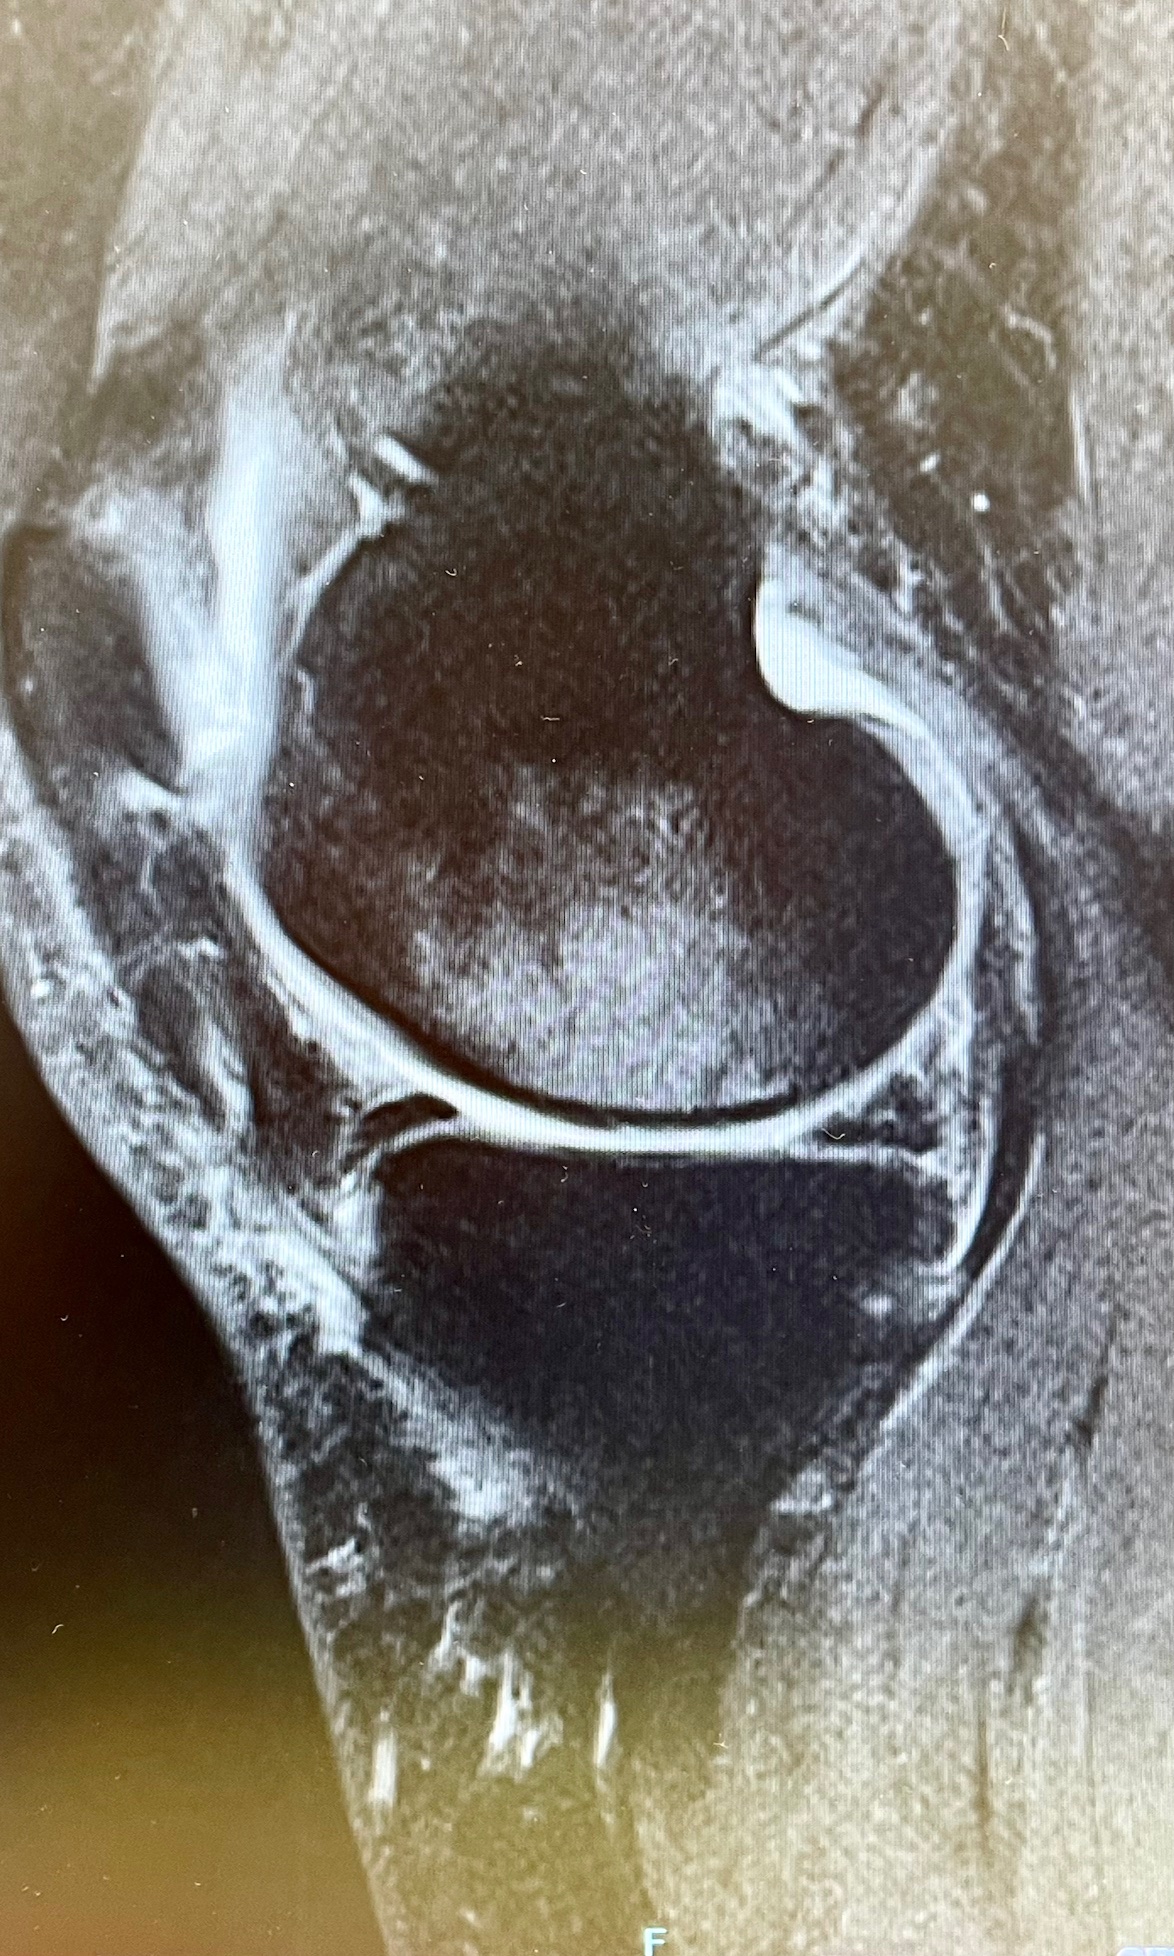

| Stage2 MRI脂肪抑制像で広範囲に高輝度陰影+ |